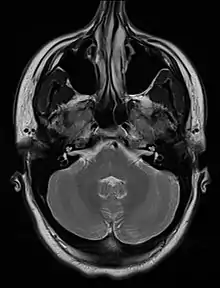

An MRI image showing a congenitally deviated nasal septum

An MRI image showing a congenitally deviated nasal septum, bowed to the left between the eye sockets